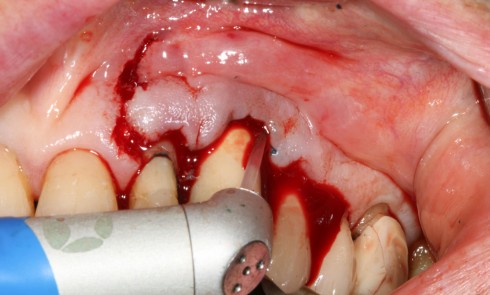

Article réservé à nos abonnés Traitement de la péri-implantite par décontamination électrolytique et régénération osseuse guidée

La patiente 65 ans ASA type I Pas de problèmes systémiques Pas de prise de médicaments Pas de consommation de...